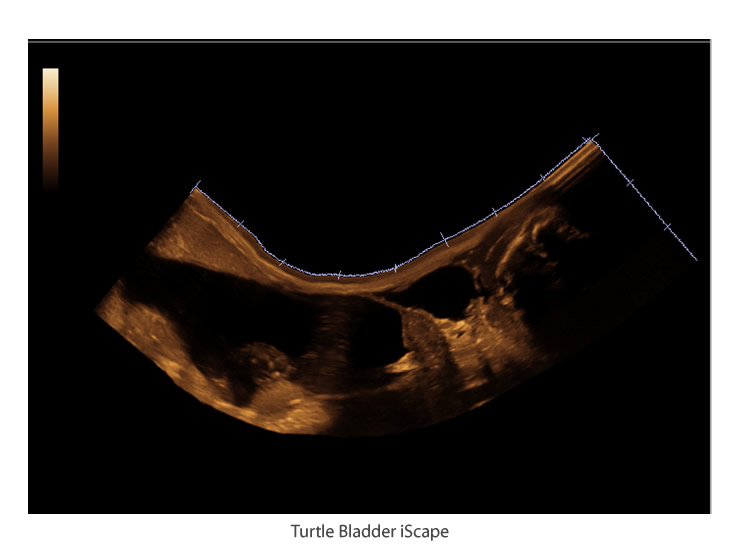

iScape™

Get a complete and extended view of the anatomical structure through panoramic imaging coupled with velocity indication and forward/backward scan ability making scanning much more accessible , smoother, and more controllable.